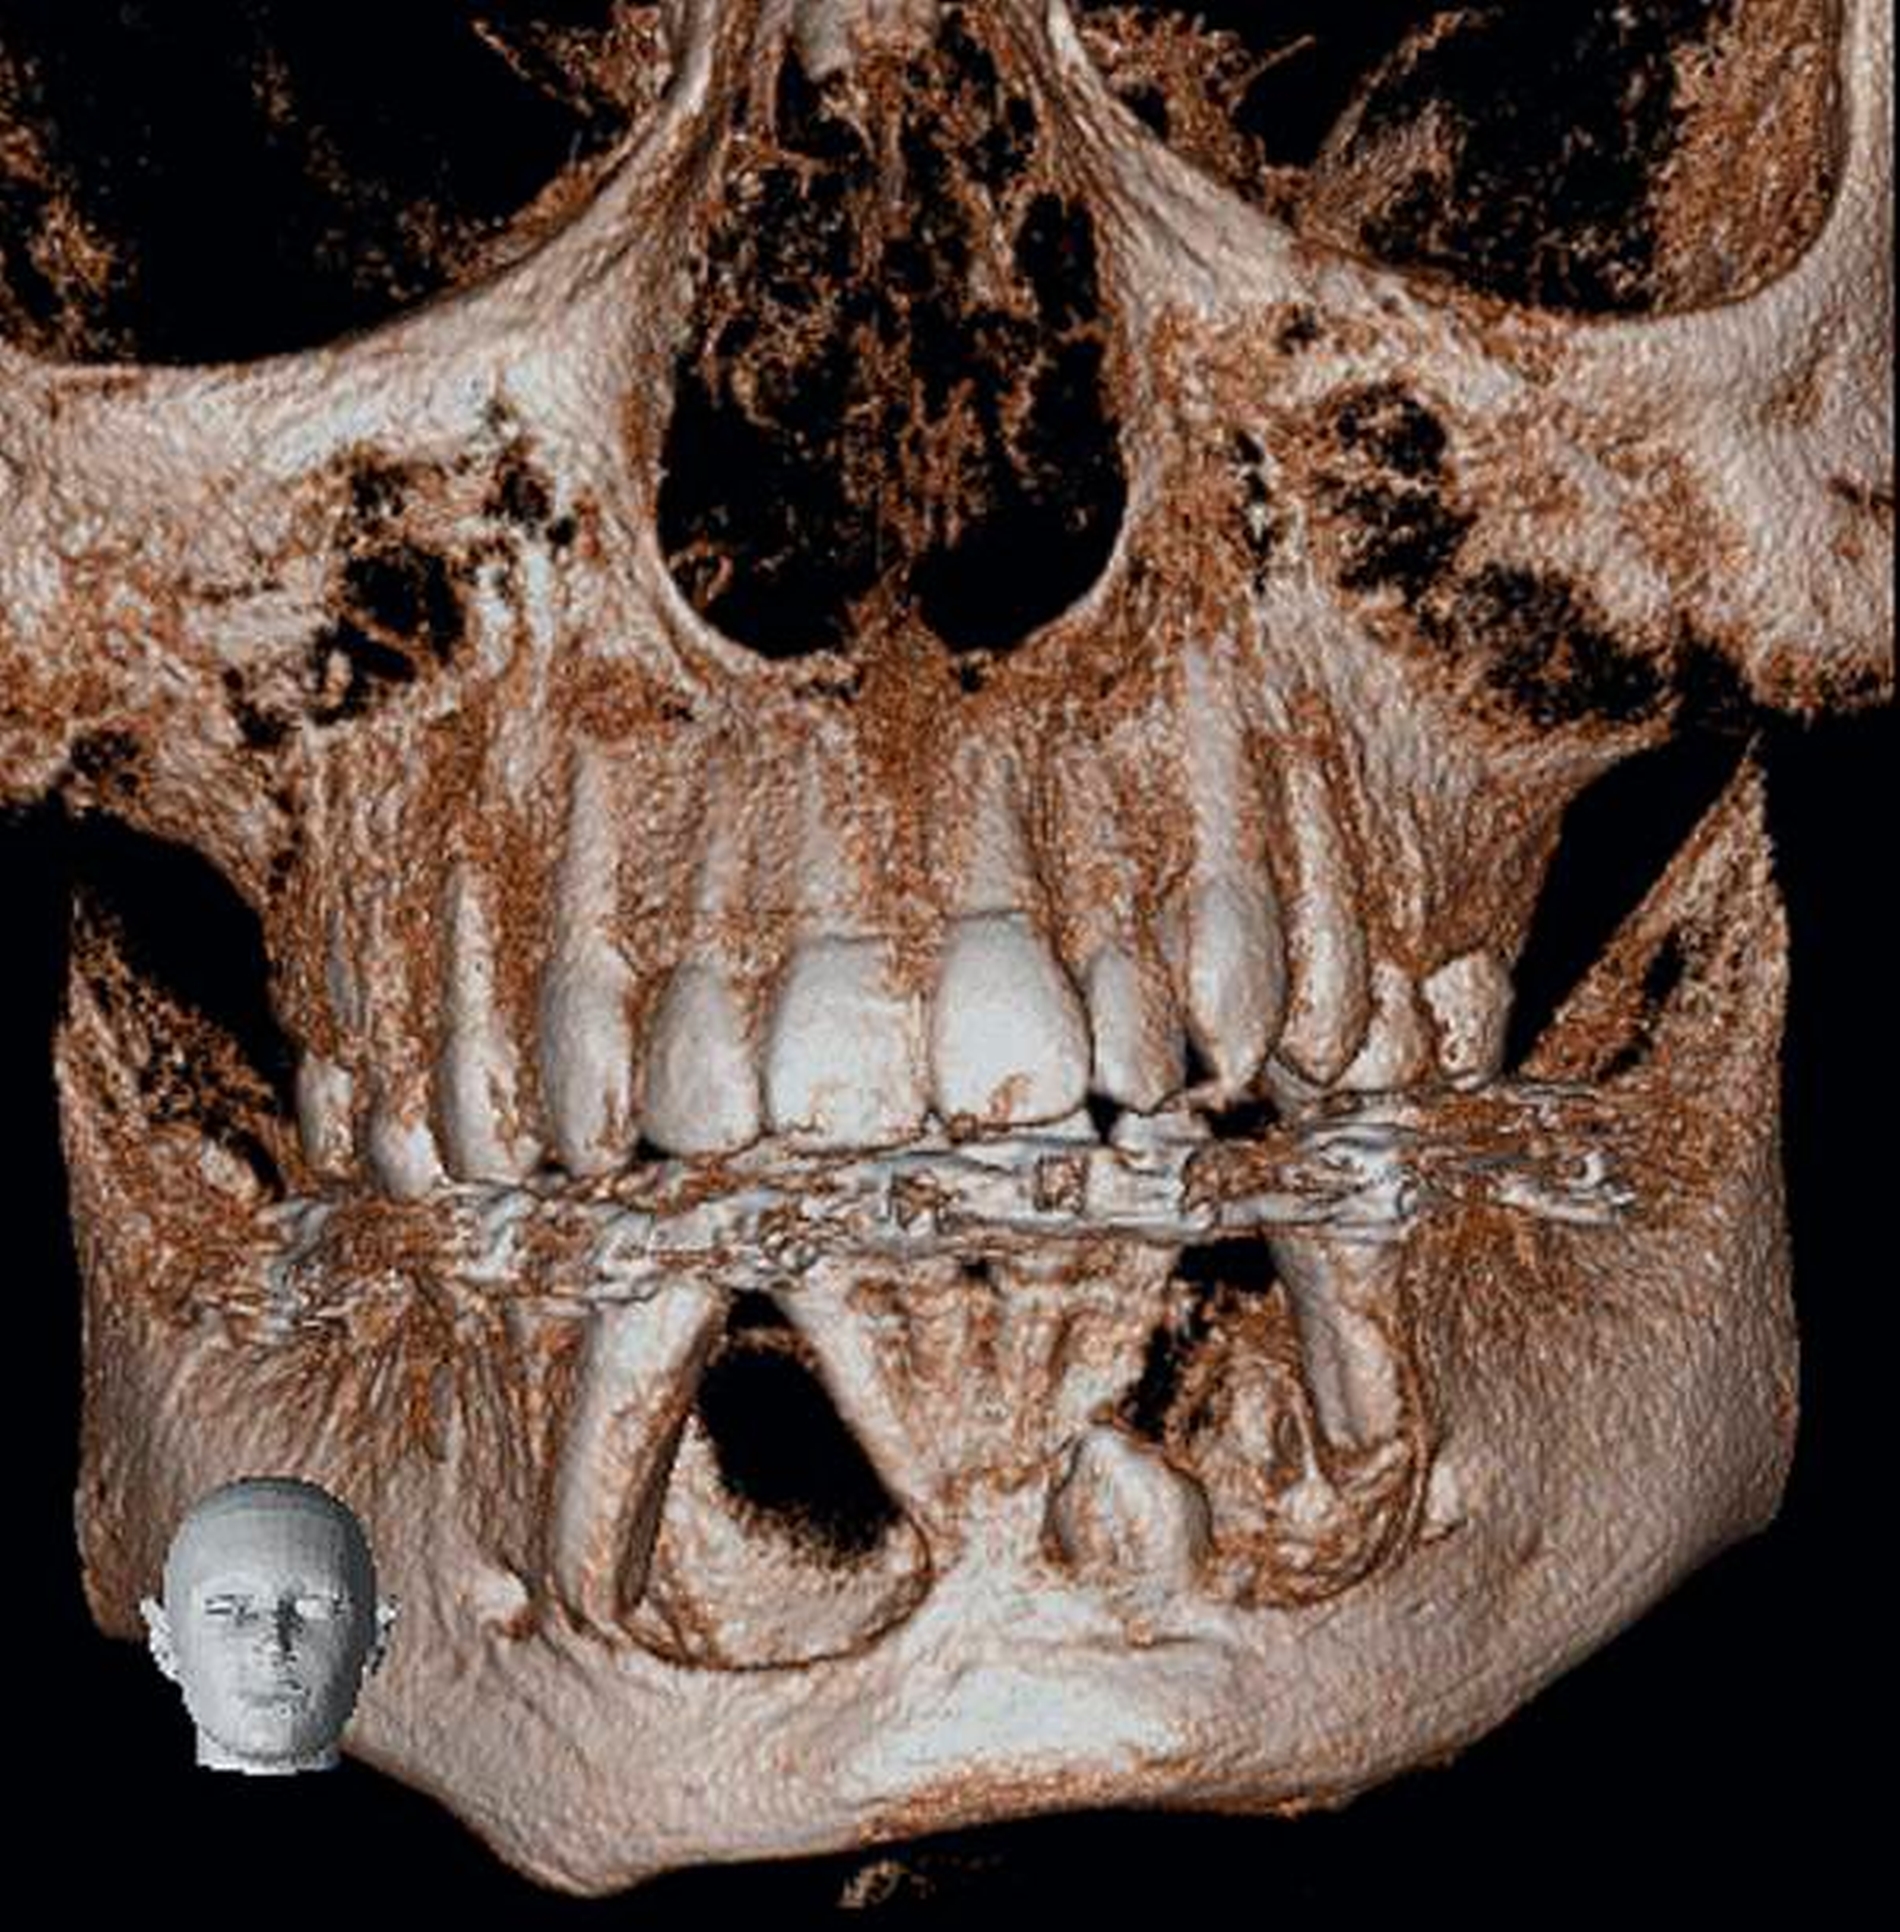

Radiologischer Befund

Im OPG (Abbildung 1) sowie in der DVT (Abbildungen 2 bis 5) imponieren zwei scharf begrenzte osteolytische Befunde im Bereich der anterioren Mandibula regio 34–32 und 41–43. Der retinierte Zahn 33 liegt basal im Lumen der Aufhellung.